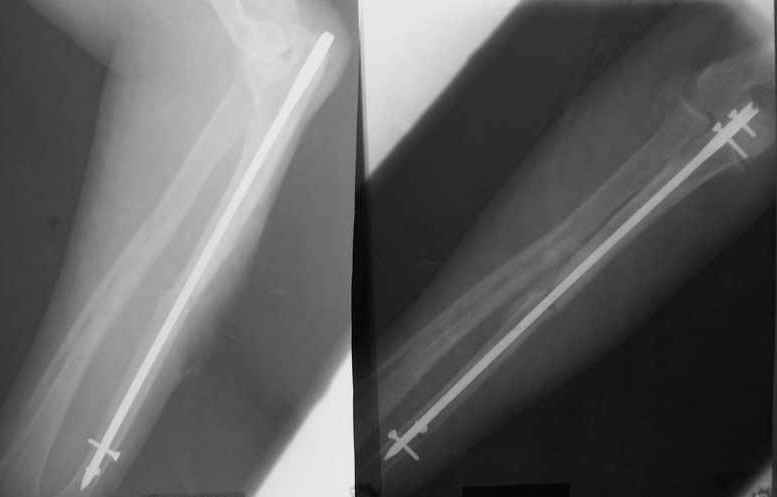

Уважаемые коллеги!Доводим до Вашего сведения наш скромный опыт применения блокирующего остеосинтеза локтевой кости (4случая), четверо пациентов с ложными суставами локтевой кости. Во всех случаях оперировали открыто с костной аутопластикой.Технических проблем введения штифтов не было. В одном случае отвалилась резьбовая часть спицы при прокс. блоке (оставлена как блокирующий винт). Дистальное блокирование осуществляли используя вместо кондуктора сп. Киршнера изгибая ее конец о край кондуктора на необходимую длину до отверстий. Наши первые впечатления классные. Очень быстрая функциональная реабилитация без гипса и консолидация через 2 мц. На представленных фотографиях двое пациентов.Тот, у которого якобы не срастается лучевая кость на АО пластине, уже катался на горн. лыжах, а сейчас опять уехал на Эльбрус -экстремал ,,,нов. С уважением Нагога Александр, ортопедическая клиника ОРТО, Самара.

Эта конкретная больная на пятый день после операции мыла дома пол (муж - хирург, не мог же он этим заниматься :-)

А движения как раз начинаются максимально рано, на следующий день, включая ротацию - больших ран ведь нет, сильно не болит - в приложении картина в день снятия швов.

К месяцу после операции практически у всех больных - клиническая картина здорового человека.

Так что стабильность достаточная. А то, что она не абсолютная, как с пластинкой - это как раз способствует периостальному сращению. Конечно, при многооскольчатых переломах для осевой устойчивости лучше запирать винтами.